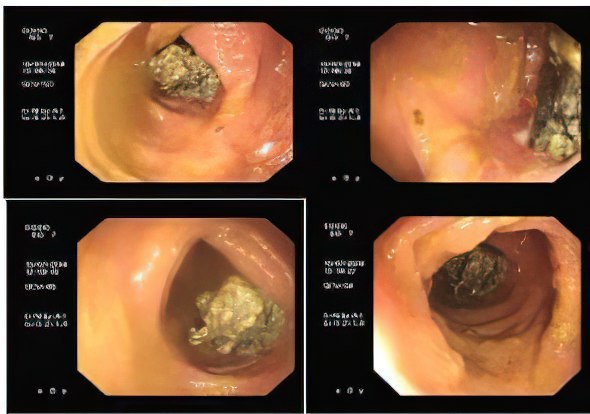

4. Siatka wrasta do sąsiednich narządów

Wszczepiona siatka powoduje reakcję organizmu – miejscowy stan zapalny. Nie jest to złe, gdyż dzięki temu siatka silnie przyrasta w miejscu wszczepienia. Niebezpieczeństwo powstaje, gdy siatka uwalnia się z miejsca jej umocowania oraz przemieszcza się w jamie brzusznej. Najczęściej siatka przedostaje się do pęcherza moczowego, ale może też dostać się do jelita cienkiego, grubego czy też innego narządu. Proces taki trwa wiele miesięcy lub lat. W tym czasie pacjent źle się czuje, ma stale bóle brzucha. Gdy siatka dostaje się do pęcherza objawem jest nawracające zapalenie. Gdy siatka przedostaje się do jelita – utrudnia przechodzenie treści jelitowej.